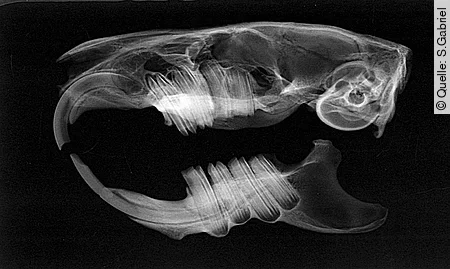

Die intraoralen Aspekte der Backenzähne lassen sich durch Inspektion mit dem Trichterotoskop oder dem Video-Endoskop nur unzureichend einsehen. Bei vollständiger Exploration der Maulhöhle in Narkose nach Einsetzen von Kiefer- und Wangenspreizern können pathologische Zahnspitzen, Zahnverbiegungen und -dislokationen diagnostiziert werden. Da aber der größte Teil des Backenzahns im Kiefer liegt, können der gesamte Zahn und seine Umgebung erst durch die Röntgendiagnostik beurteilt werden.

Eine überlagerungsfreie Darstellung aller Backenzähne ist am Schädel des Kleinsäugers nicht möglich. Daher müssen hochauflösende Röntgenbilder (Abb. [2]) bei standardisierter Lagerung in mehreren Ebenen angefertigt werden, um Zähne und Kiefer sicher beurteilen zu können. Die in diesem Artikel dargestellten CT-Bilder wurden experimentell mit einem Mikro-CT aus der Werkstoffprüfung an Knochenpräparaten angefertigt (Abb. [3]). Sie sind in ihrer Auflösung nicht mit den üblicherweise vorhandenen klinischen CT-Bildern vergleichbar. Gerade für die feinen und feinsten Veränderungen an Zähnen und Kiefern ist die klassische (Dental-)Röntgentechnik immer noch unübertroffen [[5]]. Zur isolierten Darstellung der Unterkieferäste wird eine Schrägprojektion mit einer Kippung von etwa 40° verwendet.